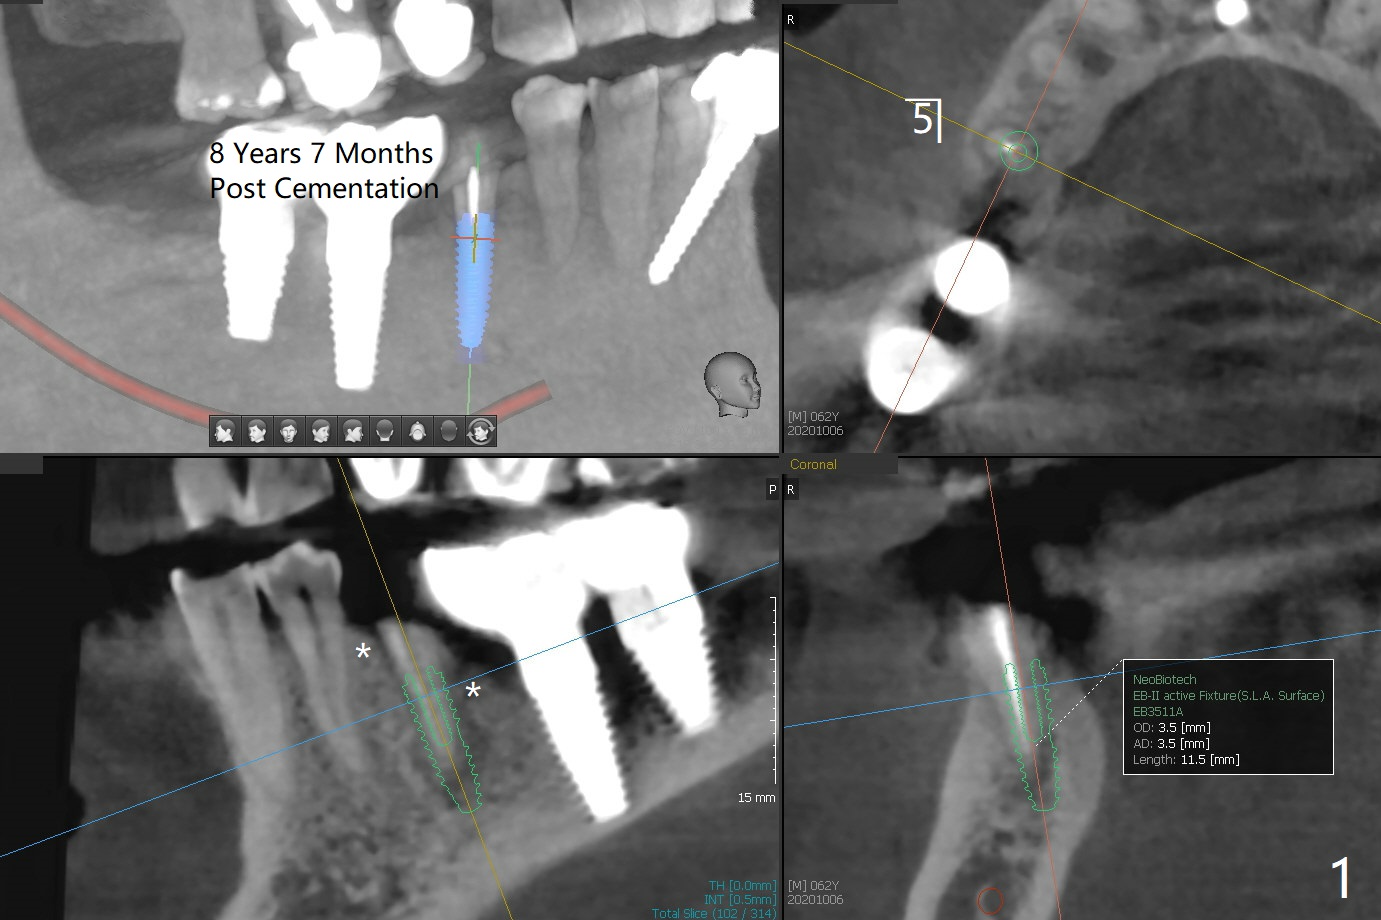

近远中牙槽嵴不在一个平面

62岁男右下6,7植牙牙冠粘固后8年7月,5牙冠脱落,近中龈下继发性龋齿,似乎适合拔除种植(图一),但是近远中牙槽嵴不在一个平面(*),远中牙槽嵴可能需要植骨,而近中使用profile drill。如果植入软组织水平植体,它大小4.5x14毫米。